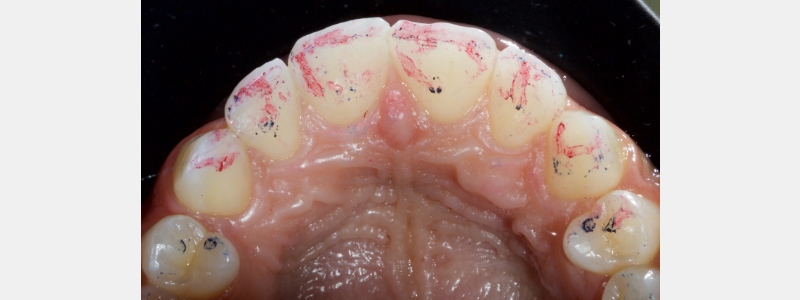

The solution is simple. After tooth preparation and before bonding, apply the stent to the tooth intraorally (Fig. 20).

A thin, sharp, flat plastic is run along the fracture line to create a fine score on the PVS stent (Fig. 21).

It’s essential that the score be minimal and not gouge. Deep gouging tends to create PVS debris and can be erroneously incorporated into the final restoration (Fig. 22).

The achromatic resin that creates the shell is layered on the stent 2.0 mm apically beyond the score line. In my experience, this is the sweet spot for how much resin to apply.